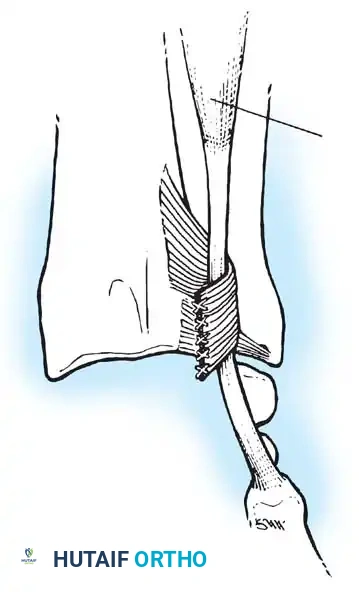

Transosseous Repair Technique:

1. Identify the foveal detachment arthroscopically or via an open dorsal ulnar approach.

2. Prepare the ulnar fovea down to bleeding bone using a burr or curette to stimulate a healing response.

3. Utilize a targeting guide to drill two converging osseous tunnels from the ulnar neck into the fovea.

Passing non-absorbable sutures through the osseous tunnels in the ulna to capture the peripheral edge of the TFCC.

- Pass strong, non-absorbable sutures (e.g., 2-0 FiberWire) through the TFCC using an outside-in or inside-out technique, then shuttle the suture limbs down the osseous tunnels.

The sutures are tied securely over the cortical bone bridge of the ulnar neck, restoring tension to the radioulnar ligaments.

- Tie the sutures over the ulnar cortical bridge with the forearm in neutral rotation to restore anatomic tension.

In cases of severe instability or concomitant ECU subsheath disruption, open capsular repair and ECU stabilization are required.

Open repair of the dorsal capsule and TFCC, ensuring robust closure and stabilization of the ulnar-sided structures.

Stabilization of the ECU tendon and subsheath, a critical step in addressing complex ulnar-sided wrist trauma.